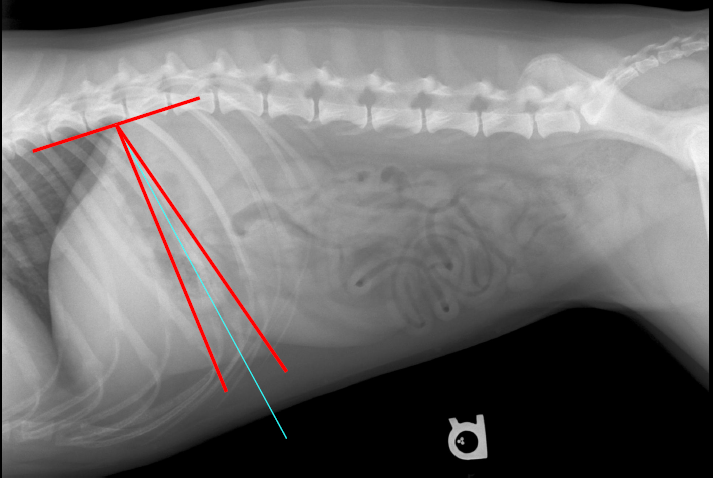

Line drawn through the fundus to the pylorus

What should the gastric axis be parallel/perpendicular to?

Should be parallel with the ribs and perpendicular to the spine

Is there something wrong with this radiograph?

Nope! The gastric axis is within the reference lines